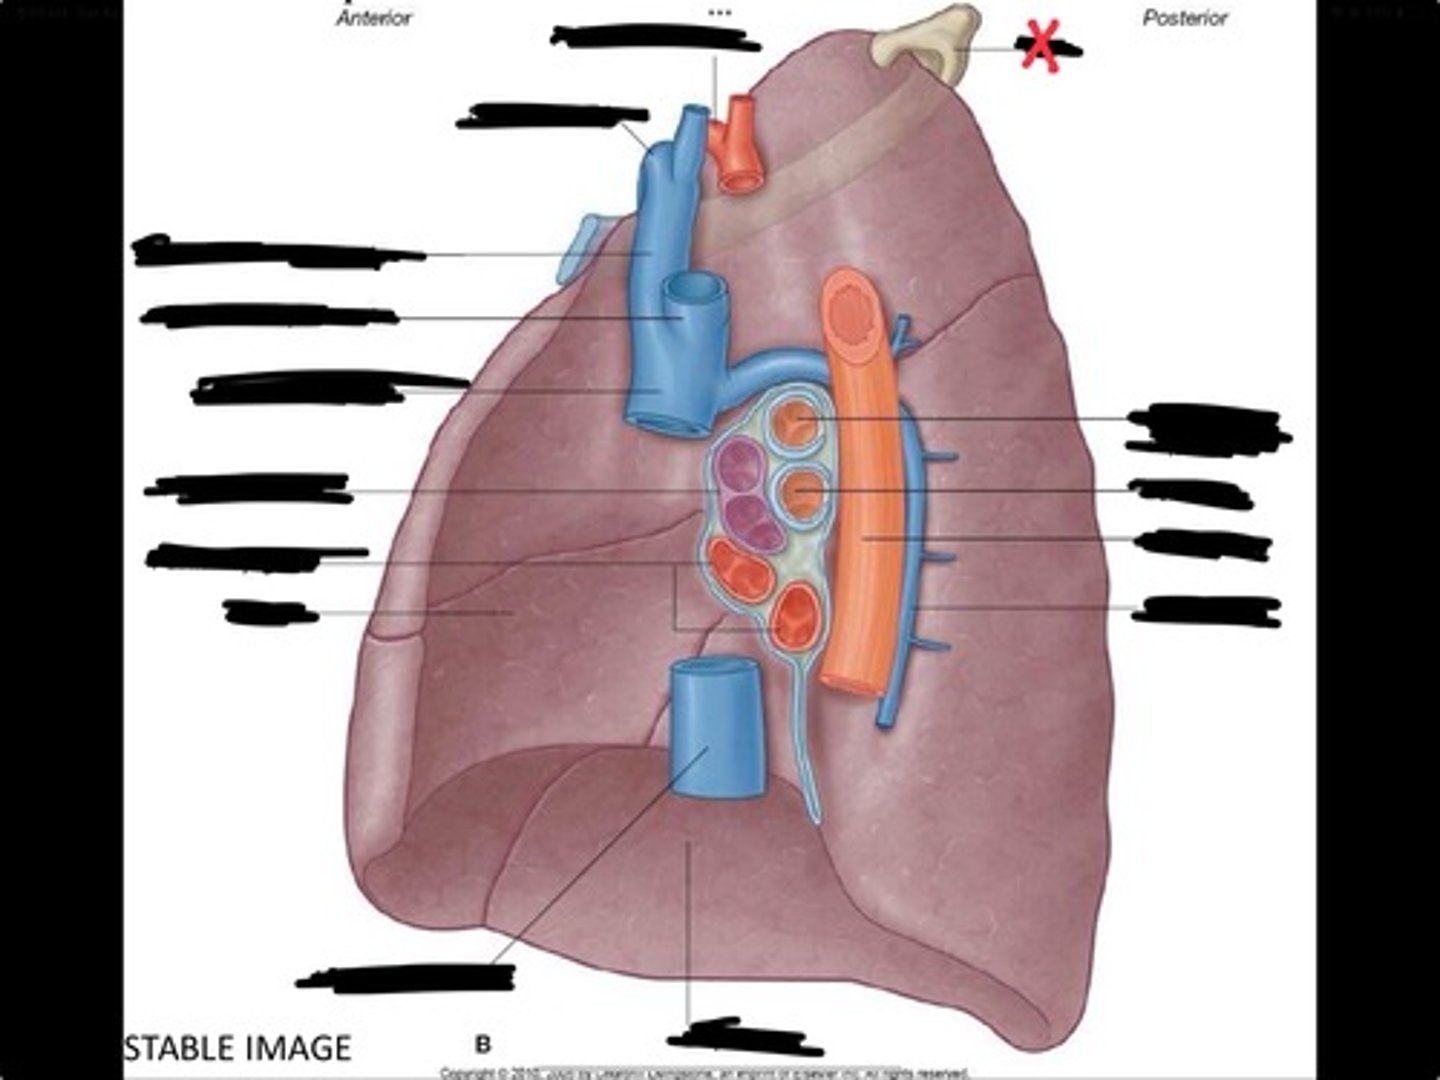

Pulmonary artery

Bronchus to superior lobe

Pulmonary veins